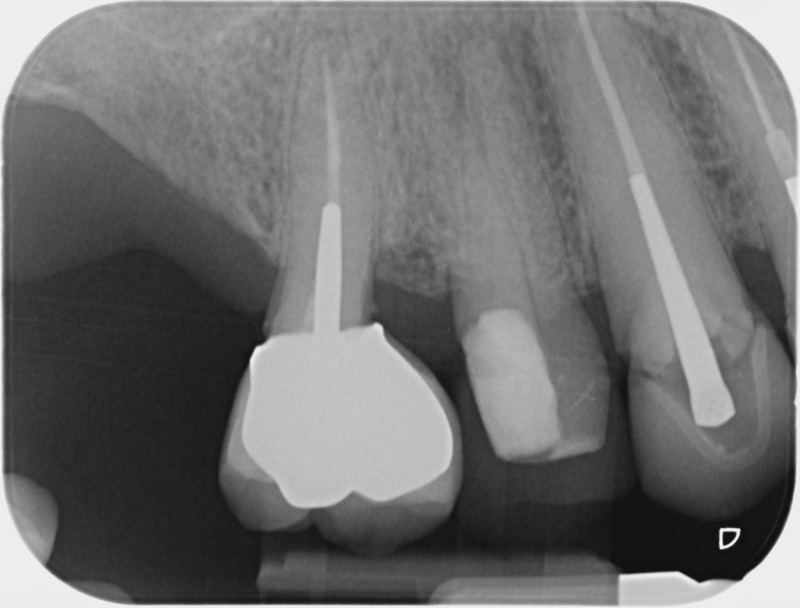

• Couronnes céramiques : Ce sont des prothèses dentaires esthétiques, avec parfois une armature métallique, destinées à rétablir l’anatomie fortement délabrée d’une couronne dentaire naturelle. Une fracture ou une lésion carieuse peut sérieusement endommager une dent qui aura alors besoin d’une couronne périphérique artificielle pour assurer sa conservation. Le soin dit de « dévitalisation » ne prévoit pas systématiquement la protection de la dent par une couronne, l’indication est à évaluer en fonction de la perte de tissu dentaire. De la même manière une dent vivante peut nécessiter la pose d’une couronne céramique sans que nous envisagions de retirer le nerf de ses racines. La couronne « tout céramique », en plus de permettre une reproduction fidèle et esthétique de l’anatomie dentaire, assure un grand confort au patient par sa biocompatibilité.

Après